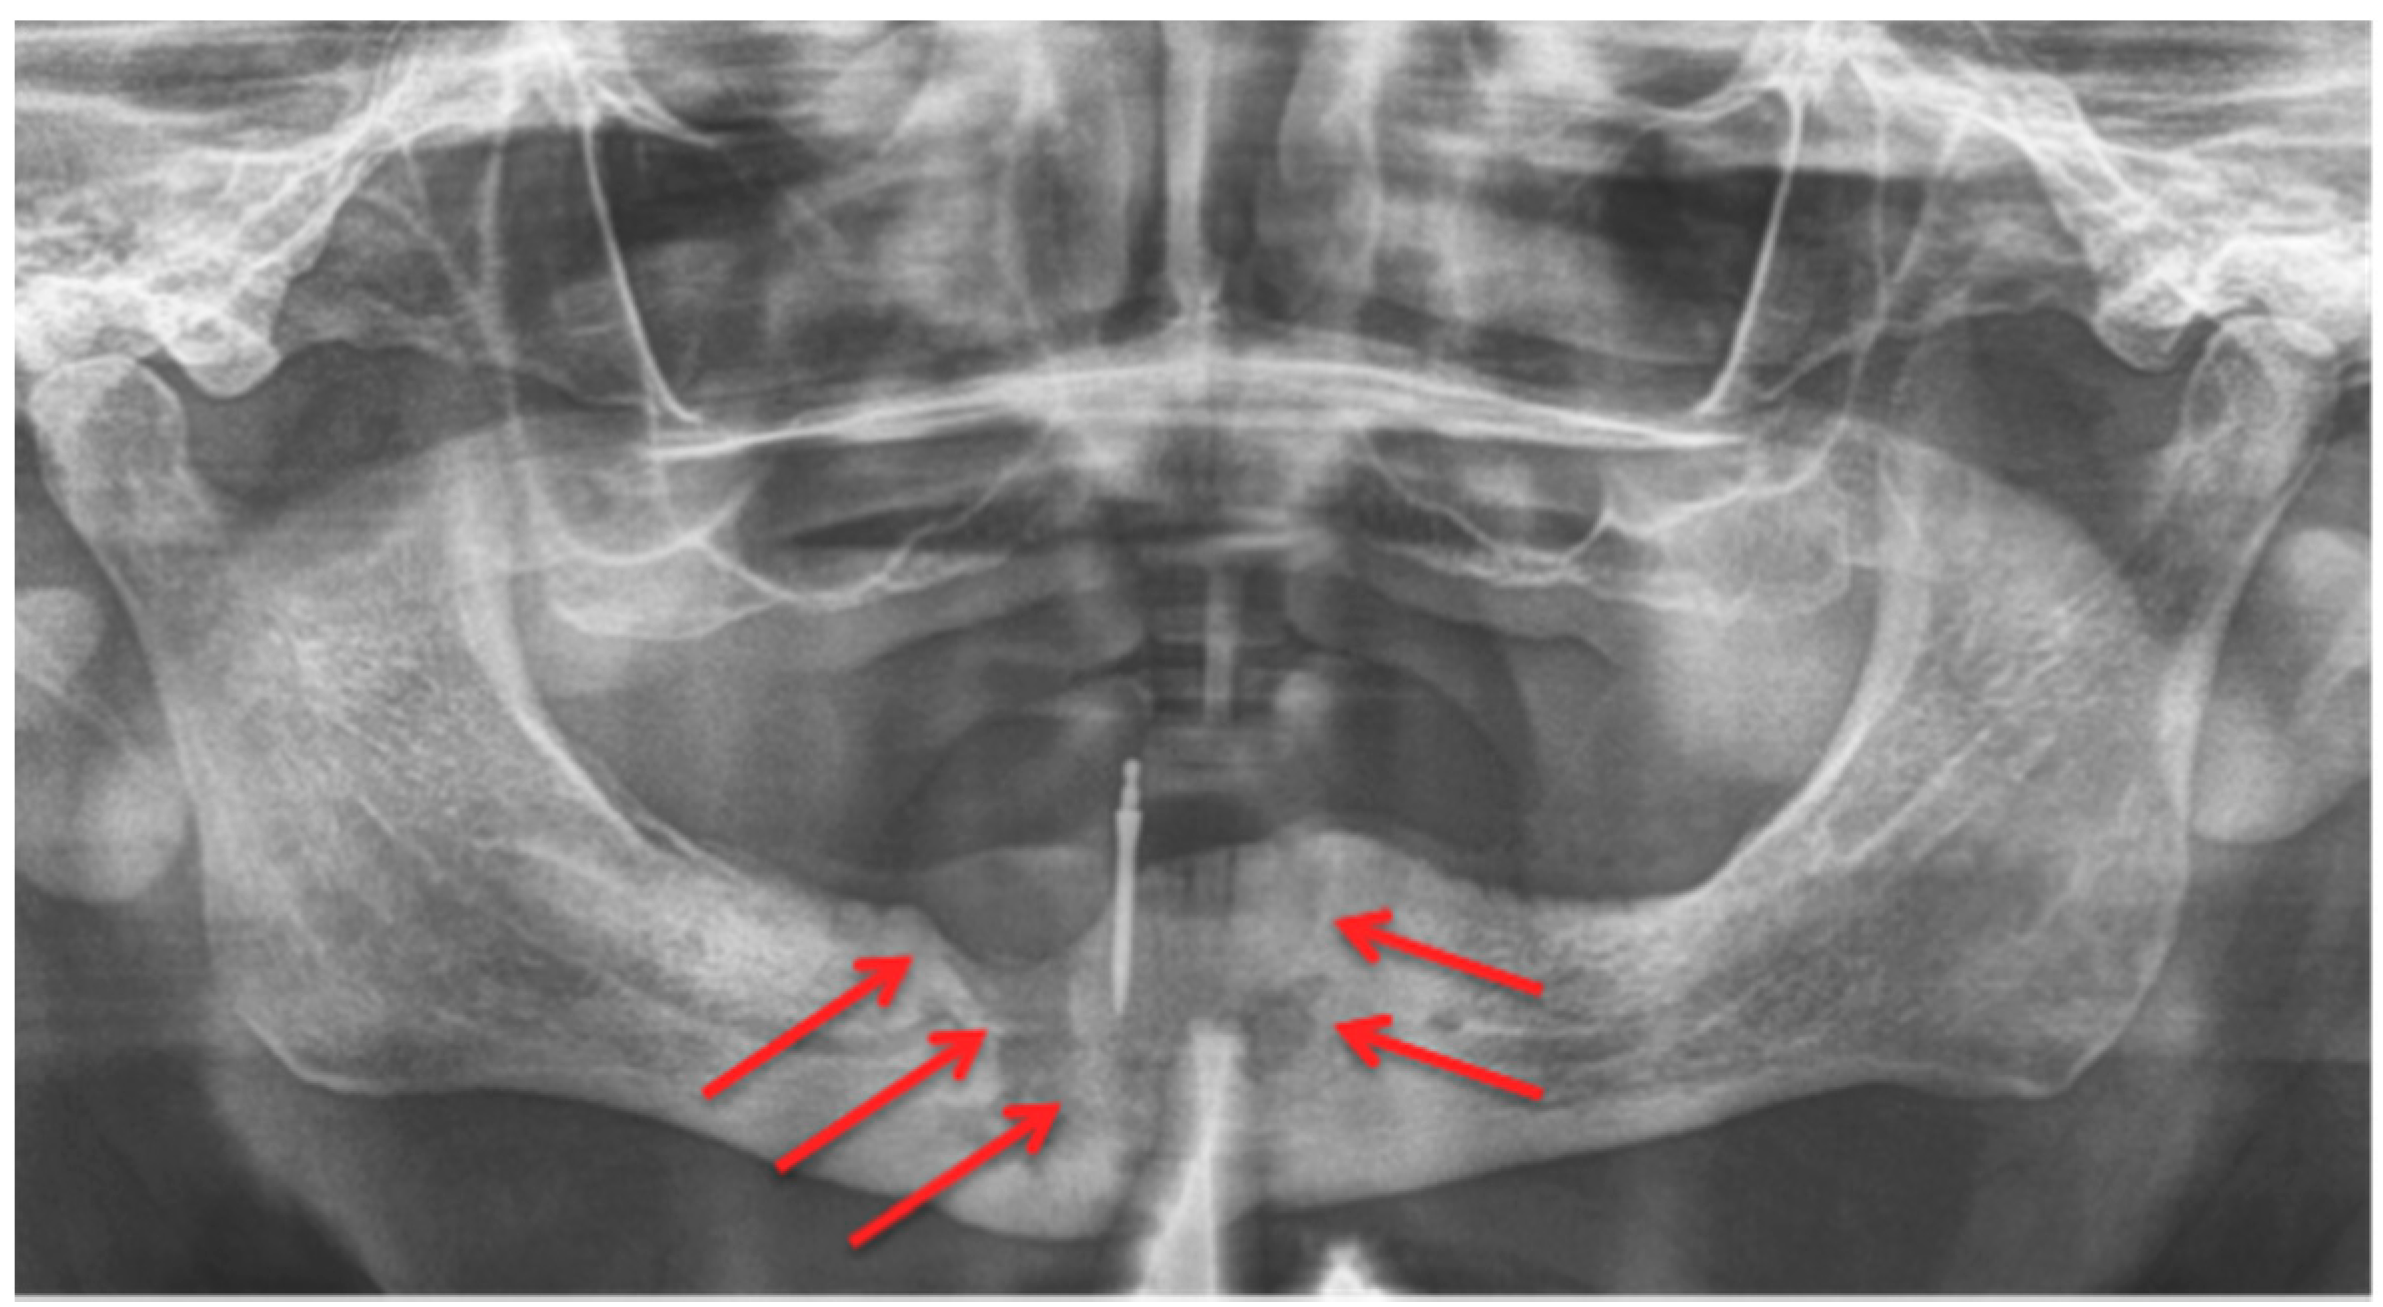

Figure 2.

Panoramic radiograph: Patient: 77 years old, male, metastatic prostate cancer, ibandronic acid & later another antiresorptive drug: denosumab. Red arrows point to the necrotic area. Artefact due to thyroid shield. For the corresponding cone-beam computed tomography (CBCT) image, see Figure 4. AAMOS staging: stage 2.